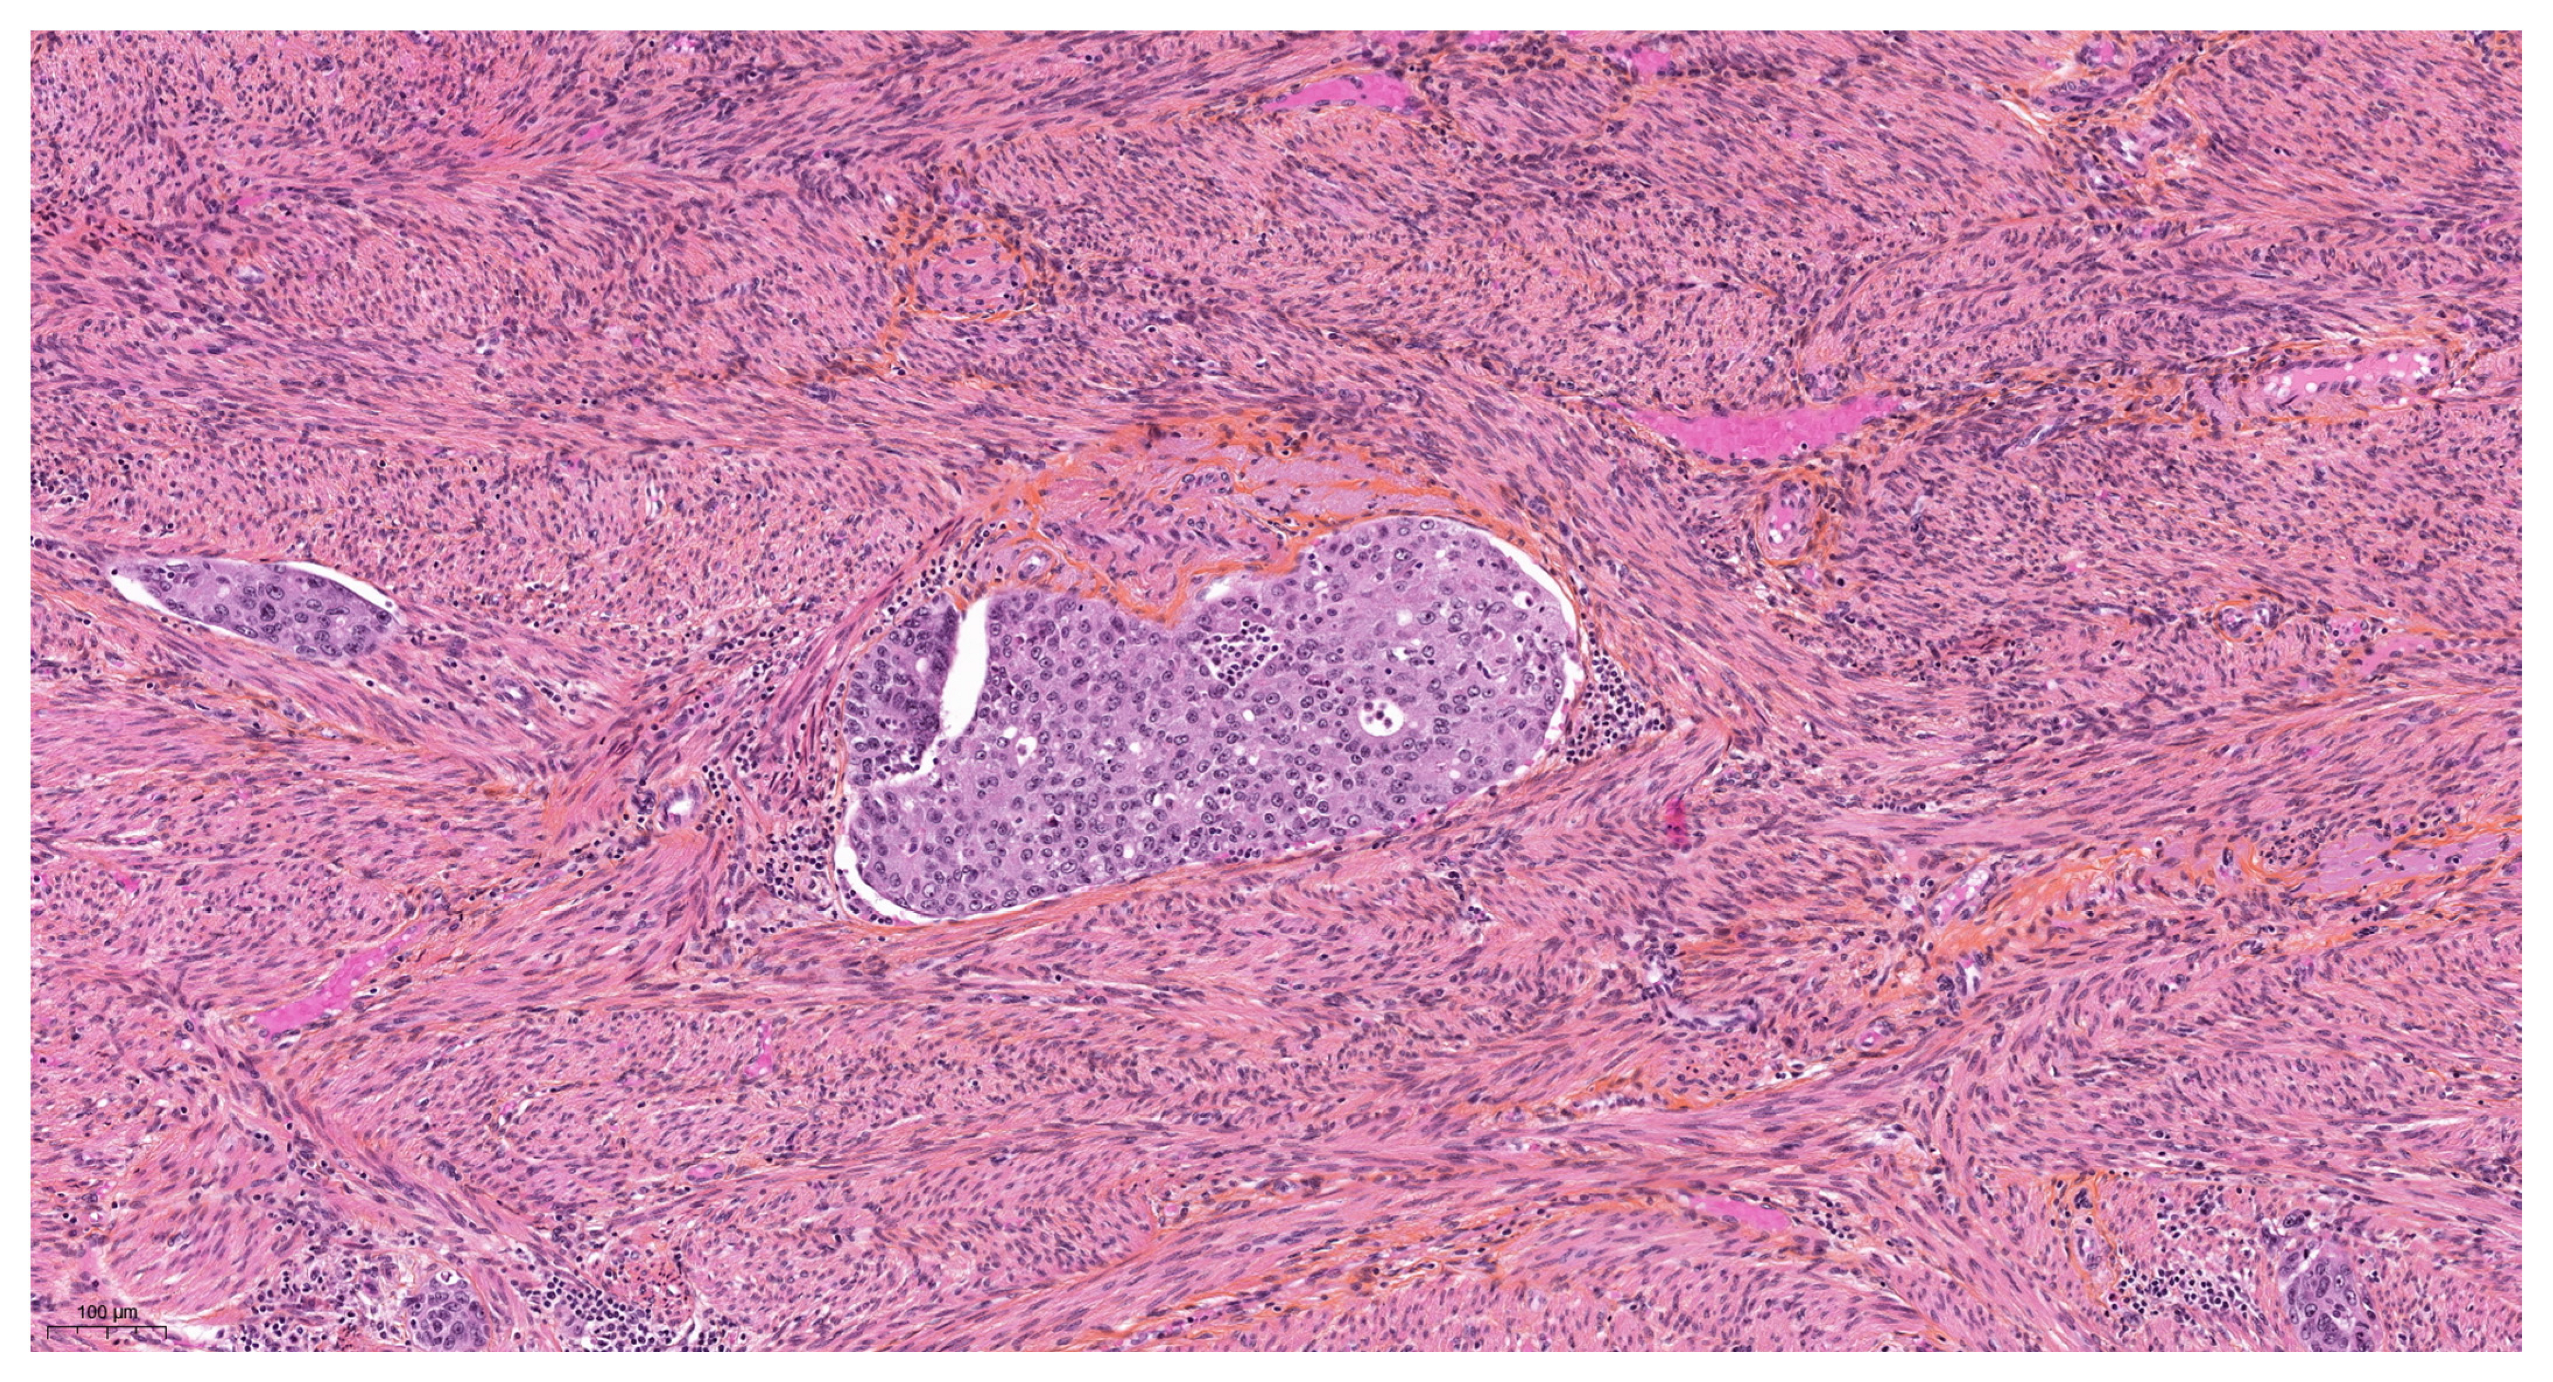

Artefacts in Hysterectomies with a Special Focus on Vascular Pseudoinvasion

| Myometrial clefts | |

| Present | 16 (26.7) |

| Absent | 44 (73.3) |